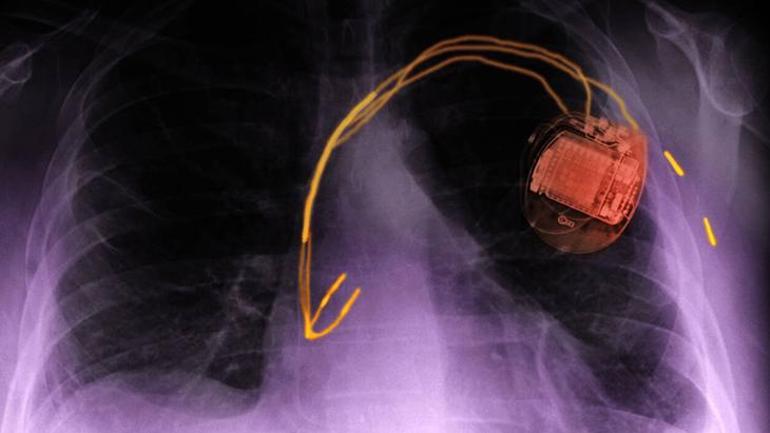

Kalp pilleri ve defibrilatörler kalp ritmi bozuklukları yahut kalp yetmezliği olan hastaları tedavi etmek için kullanılan aygıtlardır. Araştırmacılar, kalp pili ile ortalama hayat müddetinin 8,5 yıl olduğunu göz önünde bulundurarak dünya çapında kalp pili takan kişi sayısının 8 milyon ile 12 milyon civarında olmasının beklenen olduğunu belirtiyor.

Elektrikli araçların şarj müddetini kısaltmak için 350 kW’a kadar güç sağlayan yüksek güçlü şarj aygıtları geliştirildi. Yeni şarj aygıtları daha yüksek güç iletimi sağlayan DC (doğru akım) kullanırken, eski yahut konut tipi şarj aygıtları AC (alternatif akım) kullanır. Daha yüksek bir şarj akımıyla daha güçlü bir manyetik alan ve daha yüksek bir elektromanyetik teşebbüs riski olabilir ve bu da bir kalp pilinin ritmi durdurmasına yahut bir defibrilatörün uygunsuz bir biçimde ağrılı şok tedavisi vermesine neden olabilir.